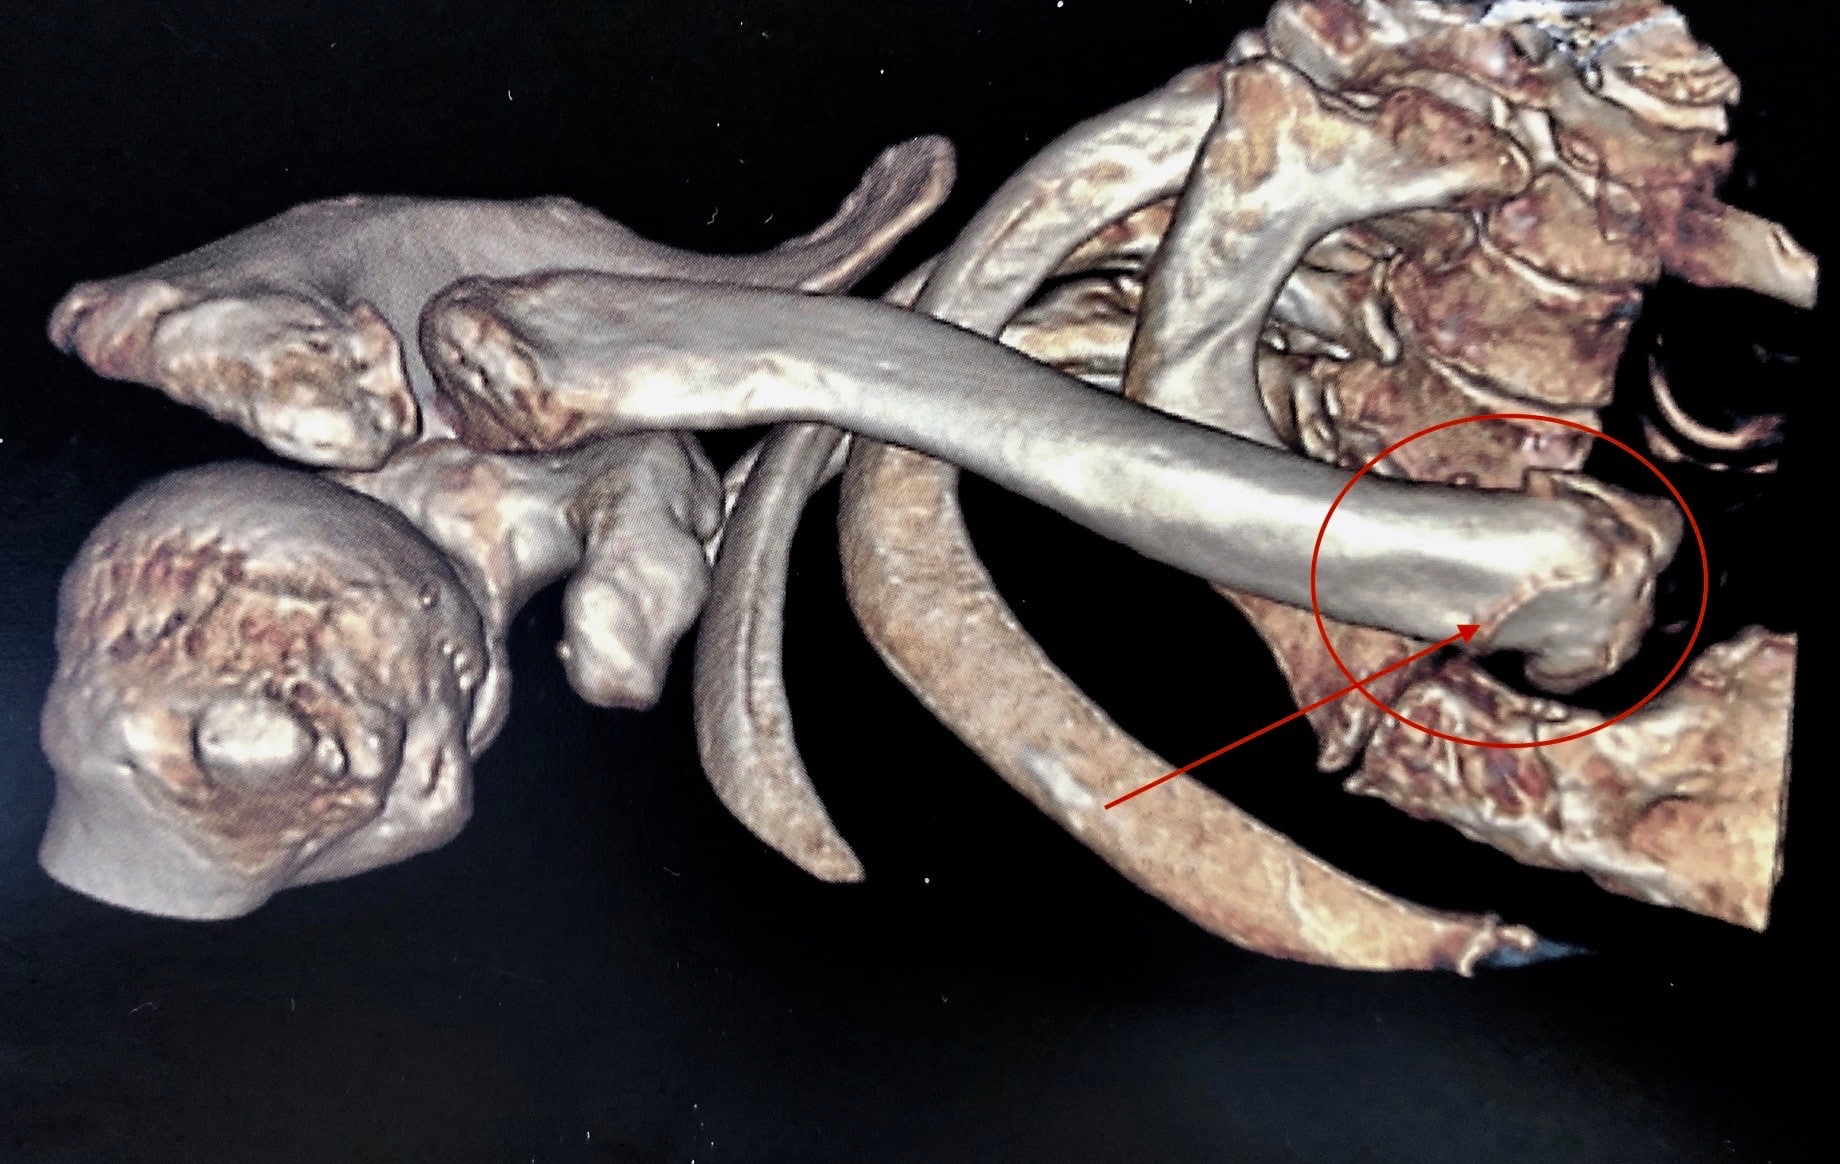

Fractures complexes

Associant les différents traits décrits précédemment, les fractures complexes de l’extrémité supérieure de l’humérus peuvent être à trois ou quatre fragments.

Le diagnostic complet requiert la radiographie simple, ainsi qu’un scanner, afin de bien évaluer les différents fragments et d’apprécier la vascularisation de la tête humérale.

Suivant le déplacement et la complexité, les risques principaux sont la raideur et le risque de nécrose de la tête humérale. Quel que soit le traitement, la récupération est longue - de six mois à un an - et passe par une longue rééducation.

Le traitement est fonction de la complexité de la fracture et de l’âge du patient :

Intervention sur fractures complexes